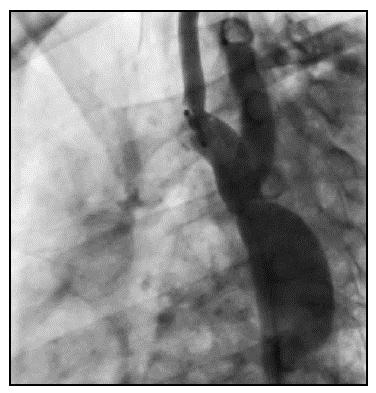

Caso 11.Trazo de onda de pulso arterial anormal para la edad, P2 mayor que P1 y AP positivo. Se evidencia que las presiones están muy elevadas para la edad, la presión central es mayor que la periférica, lo cual evidencia cambios marcados, debido a las características del sistema circulatorio. La VOP es muy elevada para la edad al igual que los índices de aumentación. Debido a las características anatómicas (coartación severa) de la paciente se explica su rigidez arterial severa y la inversión de los picos de la onda de presión (Figura 3).

Por último, se presentan dos casos de niños con coartación de aorta. La primera de 12 años, recién diagnosticada sin corrección (Figura 3) en manejo médico, y el último, es un niño de 12 años en su segundo día de corrección con stent no-cubierto (Figura 4).

De igual forma, hay cambios en la VOP en pacientes con patología mecánica de la aorta, como son los casos de disección de aorta corregida con endoprótesis o coartación de aorta, a pesar de ser, patologías y pacientes diferentes, sus componentes mecánicos se comportan de igual manera (menos distensibilidad arterial). En el caso de la corrección con endoprótesis, se observan los parámetros severamente elevados, la VOP y los índices evidencian una rigidez severa, la presión arterial central es mayor que la presión arterial periférica. Estos efectos pueden ser causados por las condiciones clínicas de la paciente y la endoprótesis persé. La endoprótesis es de un material menos elástico que la pared vascular y en este caso cubre la aorta ascendente y torácica (región con mayor distensibilidad), lo cual puede correlacionarse con la severidad de la rigidez. Este concepto puede estar presente en los casos de coartación aórtica, en donde la aorta a pesar de ser "joven y elástica", en una porción hay una gran estrechez, lo cual compromete la elasticidad y comportamiento fisiológico normal, por esta razón se puede ver como los parámetros están aumentados, las presiones, VOP y los índices son severamente elevados para la edad. En el caso del paciente después de la corrección con stent, se observa como mejoran los parámetros significativamente.